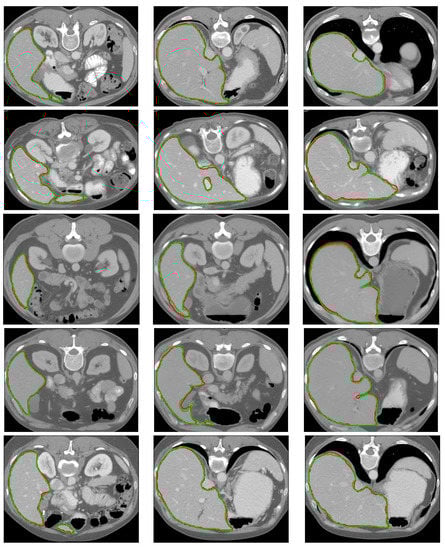

- -

3.4. Ablation Study